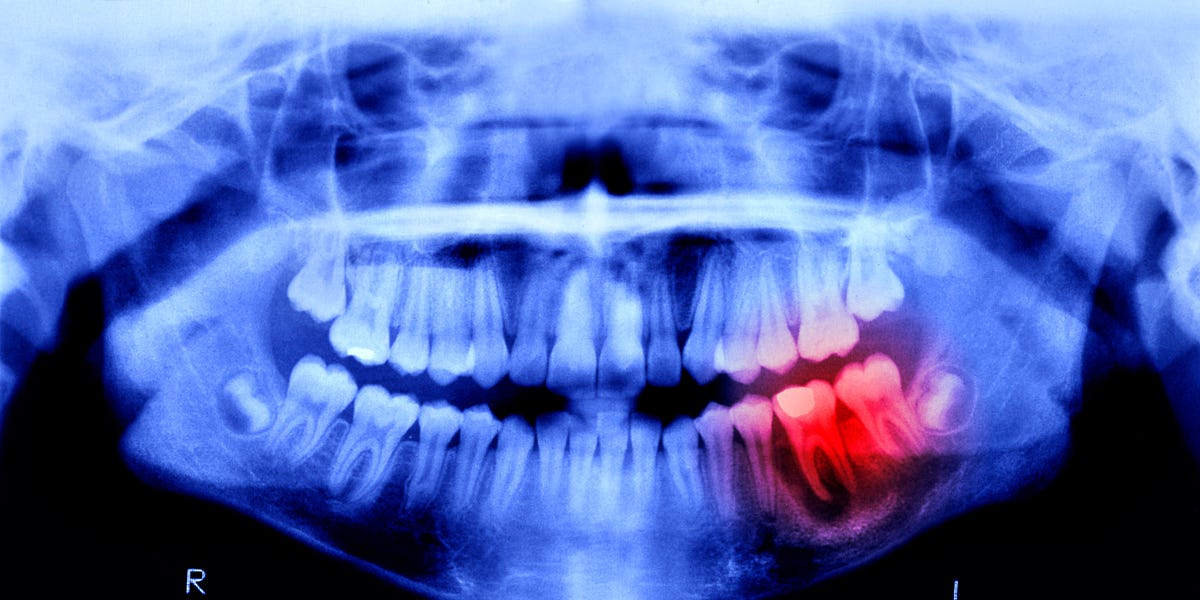

Los dientes, sin embargo, no son huesos. Aunque están formados en parte por los mismos componentes y constituyen el material más duro del cuerpo humano —gracias a su capa protectora de esmalte—, carecen de la capacidad crucial de curarse y volver a crecer por sí mismos. Pero esto podría no ser siempre así. Investigadores japoneses están avanzando con un fármaco experimental que promete regenerar dientes humanos. Los ensayos en personas comenzaron en septiembre de 2024.